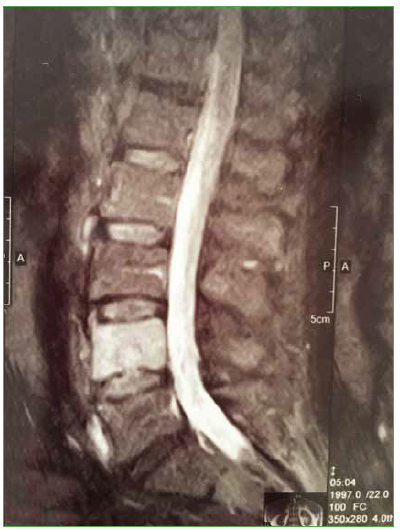

4. Wu HT, Morrison WB, Schweitzer ME. Edematous Schmorl’s nodes on thoracolumbar MR imaging: characteristic patterns and changes over time. Skeletal Radiol 2006;35:212-9. https://doi.org/10.1007/s00256-005-0068-y

14. Stabler A, Bellan M, Weiss M, Gartner C, Brossmann J, Reiser MF. MR imaging of enhancing intraosseous disk herniation (Schmorl’s nodes). AJR Am J Roentgenol 1997;168:933-8. https://doi.org/10.2214/ajr.168.4.9124143

16. Takahashi K, Miyazaki T, Ohnari H, Takino T, Tomita K. Schmorl’s nodes and low-back pain. Analysis of magnetic resonance imaging findings in symptomatic and asymptomatic individuals. Eur Spine J 1995;4:56- 9. https://doi.org/10.1007/bf00298420

17. Walters G, Coumas JM, Akins CM, Ragland RL. Magnetic resonance imaging of acute symptomatic Schmorl’s node formation. Pediatr Emerg Care 1991;7:294-6. https://doi.org/10.1097%2F00006565-199110000-00009

18. Seymour R, Williams LA, Rees JI, Lyons K, Lloyd DC. Magnetic resonance imaging of acute intraosseous disc herniation. Clin Radiol 1998;53:363-8. https://doi.org/10.1016/S0009-9260(98)80010-X